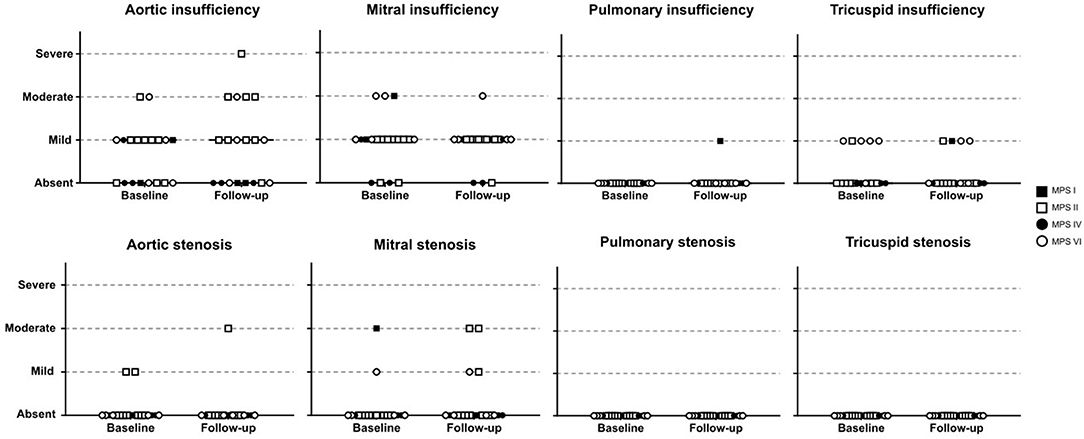

Among the 76 patients included in this study, left side valvular disease was a frequent finding, with mitral and aortic thickening being reported in most patients in all four MPS types (Figure 1). Furthermore, mitral and aortic insufficiency, mostly mild, were frequently found in patients with MPS I, II, and VI, but were also observed in a significant proportion of patients with MPS IVA. To a lesser extent, tricuspid valve thickening and insufficiency were also present in patients with MPS types I, II, and VI. Heart valve involvement was both more prevalent and more severe in adult patients (Figure 2; Table 3).

For those 19 patients whose echocardiographic measurements were available before and after ERT start (11 children and 8 adults), a significant reduction of LVH parameters (including IVST, LVPWT, and LVM) was observed after ERT was started (Figures 3G–I), a finding that was not identified in 18 patients that remained untreated with ERT (Supplementary Figure 1). However, no statistically significant changes in SPAP, LAD, or LVEF were observed after ERT (Figures 3J–L). Moreover, ERT did not lead to significant improvements in valvular disease (Figure 5).

Figure 5. Comparison of valve abnormalities before and after ERT. In the statistical analysis, with Wilcoxon matched-pairs signed rank test, no significant difference was identified.

In this study, we assessed the prevalence of cardiac manifestations in a cohort of patients with MPS I, II, IVA, and VI; which included mostly patients treated with ERT. In agreement with previous reports (3, 17–20), valve involvement comprised mainly left-sided valves and affected a high proportion of patients. Mitral valve involvement was more common than the aortic valve in the four MPS types. Valve involvement, especially aortic insufficiency and mitral stenosis, was more commonly observed in older patients. We could not identify any significant worsening or improvement of valve pathology after ERT. It is widely accepted that ERT has limited impact on valve abnormalities of patients with MPS (13, 21–25), probably due to poor tissue penetration and irreversibility of the valvar damage. Nevertheless, it may have a role in preventing or delaying its appearance when treatment is started very early, as suggested by studies with sibling pairs and animal models (26, 27).